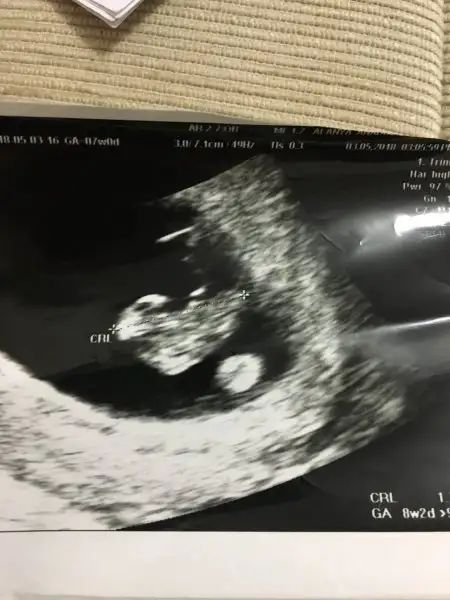

Canım ben yorum yapıcaktım ama plasentanın yerini tam belirleyemedim sağ da bir şey görüyorum sol taraftada o yüzdenKızlar bilen biri bana da yorum yapabilir mi acaba çok merak ediyorum en azından küçük bi yorum 7 haftalık karından ultrason

Ama kız demek istiyorum biraz daha o tarafta diyorum :)Canım ben yorum yapıcaktım ama plasentanın yerini tam belirleyemedim sağ da bir şey görüyorum sol taraftada o yüzden

Saol canım cevabın için bi kızım olsun çok istiyorum ama bakalım hayırlısı sağlıklı olsundaAma kız demek istiyorum biraz daha o tarafta diyorum :)

Kız cnm plasentayi net gördüm ama teori bu tabi tutar tutmaz7 haftalık karından sizce ne?

Ramzi teorisine göre ( bilimsel bir araştırma sonucuymuş ve %85 doğruluğu varmış). İlk 6-8 haftalık ultrason görüntüsüne göre bebeğin kesenin içersinde soldan ya da sağdan girişine göre cinsiyet tahmini yapılıyor. Bilimsel olunca tecrübeli annelerimiz yada anne adaylarımızdan yardım istiyoruz. Doğruluğu var mı öğrenmek adına :) Bizleri aydınlatırsanız çok seviniriz. bu teorieye göre;

Vajinal muayeneyle bakıldıysa eğer;

Sağdan girmiş gözüküyosa aslında solmuş ve ERKEK,

Soldan girmiş gözüküyosa aslında sağmış ve KIZ ,

Karından bakıldıysa eğer,

Soldan girmiş gözüküyosa gerçektede solmuş ve ERKEK,

Sağdan girmiş gözüküyosa gerçekte de sağmış ve KIZ,

o zaman bu teoriye göre kız oluyo canım onu bebek sandım ben :)